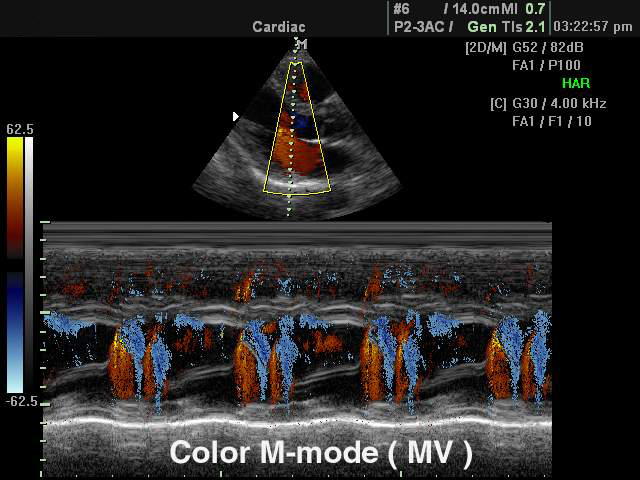

Цветной M-режим (Color M-mode) - это совмещение М-режима и режима ЦДК, при котором на графике М-режима цветокодированная составляющая изображения отображается в дополнение к серошкальной, что заметно упрощает временную оценку регургитации или рефлюкса.